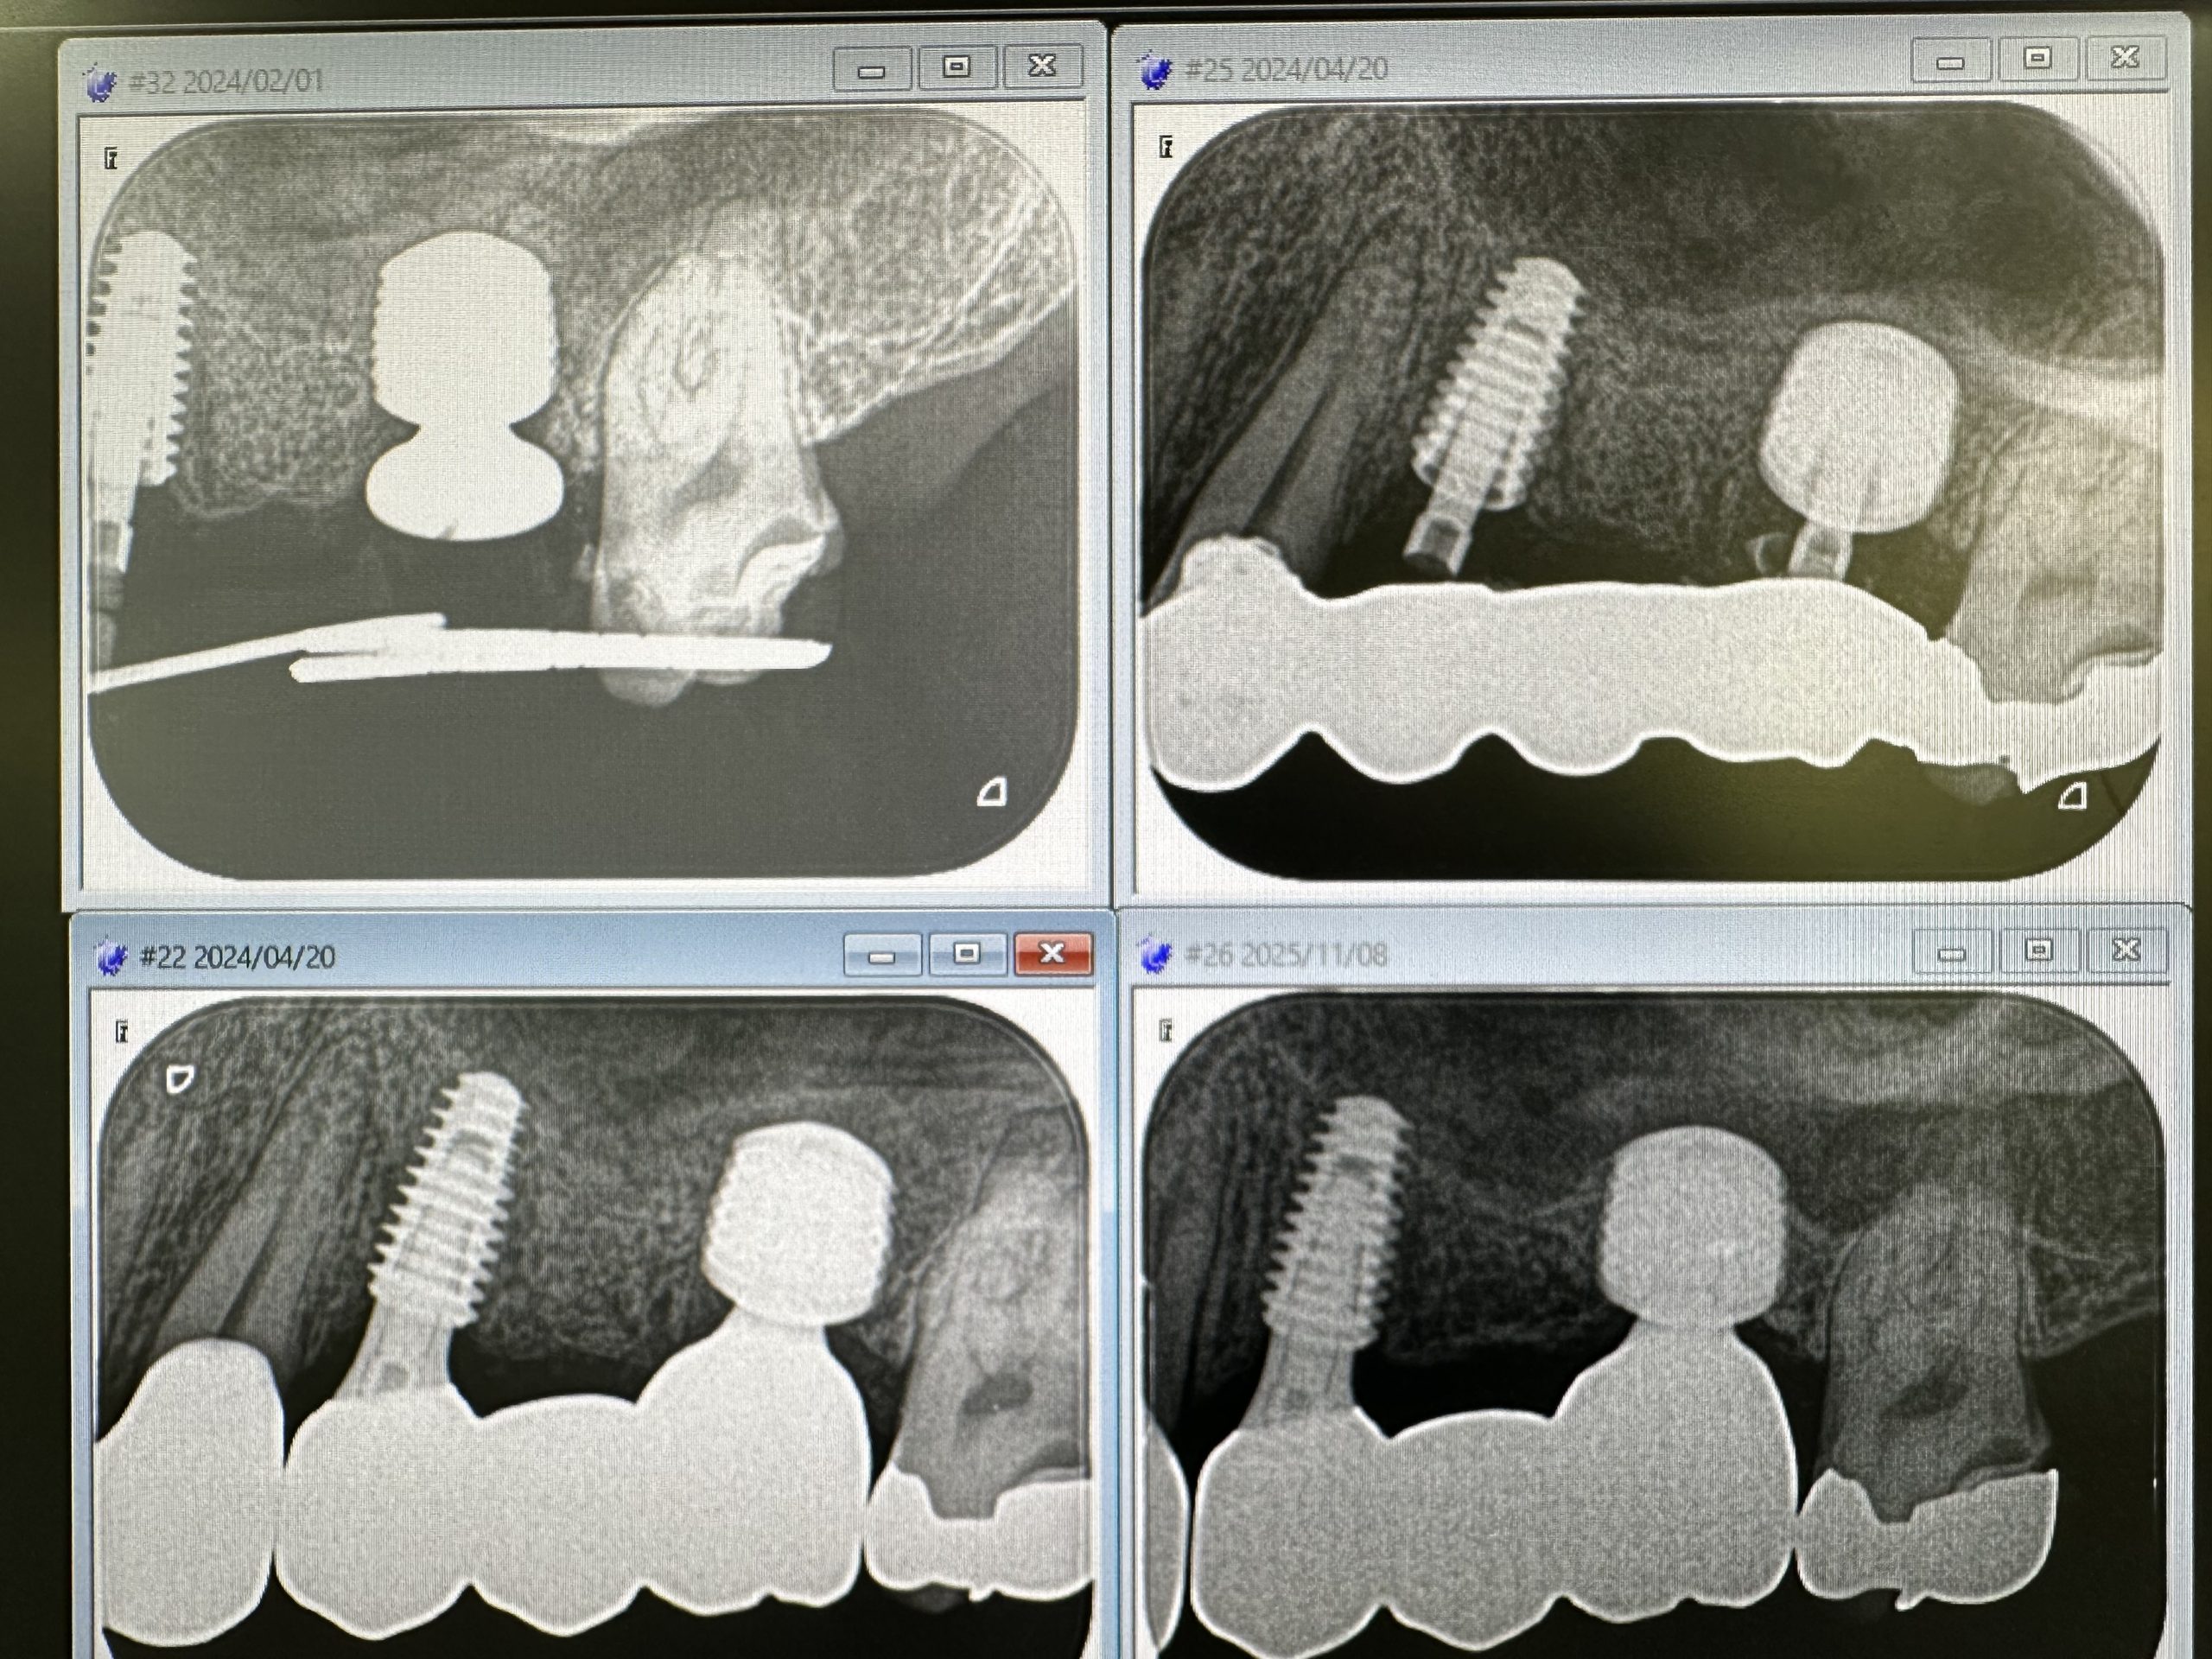

次は、インプラント定期検診

安定!💪

画像見れば変遷がなんとなくわかる

詳細は割愛